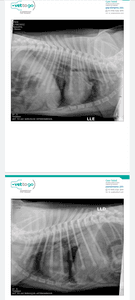

O spike foi atropelado foi atropelado  em quanto passeava, o motorista  nos prestou socorro mas logo foi embora ele teve grave fraturas no tórax  está com pneumotórax e hemorragia pulmonar. E precisa ficar entubado com intervenção  de ventilação mecânica e analgesicos  nessecita  de uma tomografia e medicamentos para estabilizar o quadro pulmonar ele precisa ficar internado por no mínimo 72h e fazer exames de rx diários para acompanhar seu quadro cada diária com aparelho medicação  e exame está 2.710 eu estou desempregada e só  meu esposo está trabalhando tenho uma filha de 6 anos que estava no momento  do acidente els esta tendo febre desde tarde não come e não está conseguindo  dormir direito passou o dia todo chorando  por causa do cachorro. Estou desesperada não sei mais oque fazer peço pelo amor de Deus  que vcs nos ajudem com o tratamento  do spike que Deus os abençoe  grandemente. #forçaspike

As 2 h da manhã o médico me enviou msg pois o Spike deu uma piorada eles precisam realizar uma tomografia para ver melhor o tamanho da lesão e fazer a drenagem do sangue que está no pulmão. Eles só liberam exames e medicames diante o pagamento o Spike está recebendo anestesia pelo soro para reduzir as dores